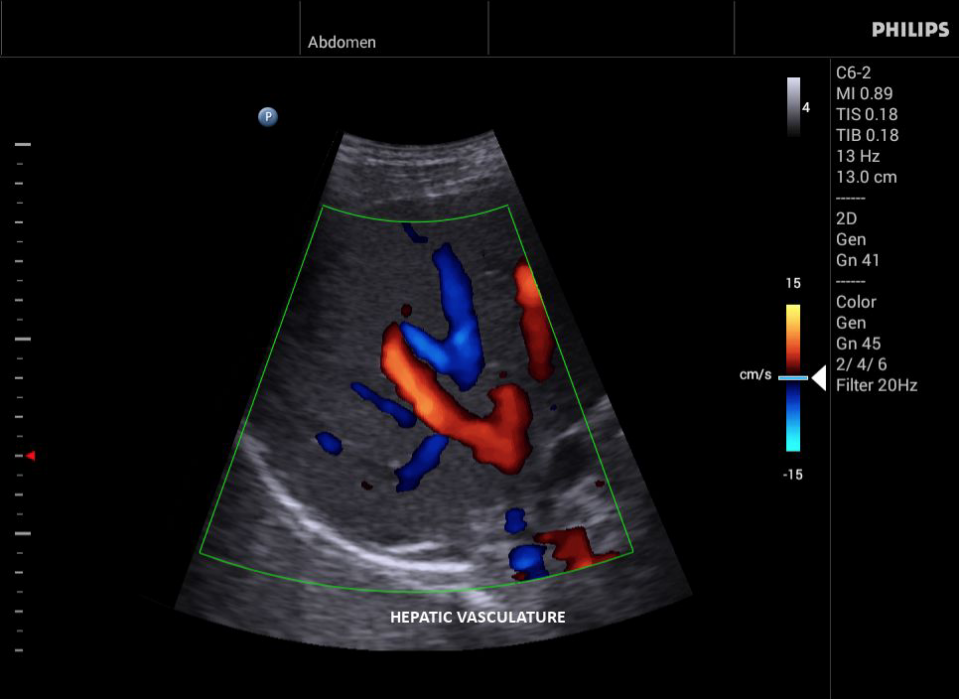

• Цветное допплеровское картирование

• Конвексный УЗИ датчик Philips C9-4v

• Конвексный УЗИ датчик Philips С6-2